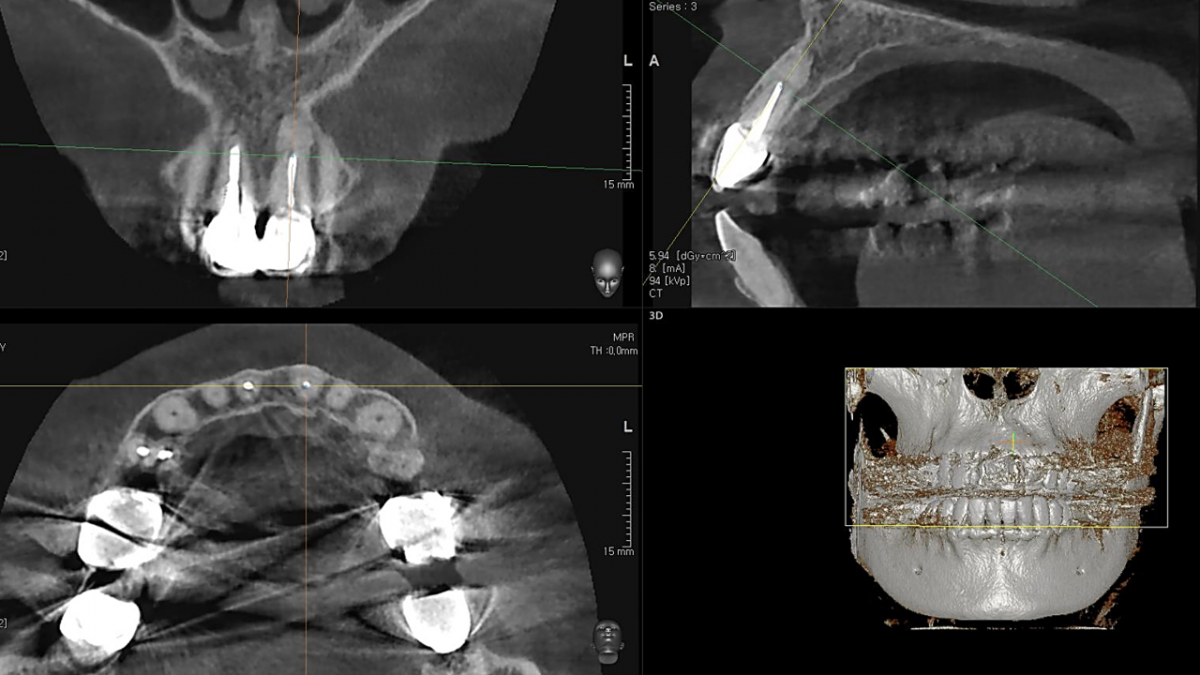

Apicorctomy /central incisor /GBR ; 6-year follow up.

<CJ SBN> Apicorctomy /central incisor /GBR ; 6-year follow up.